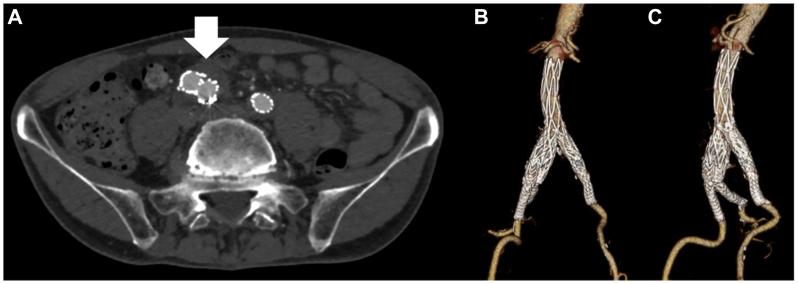

患者术后恢复顺利,CT检查未发现内漏(图3),术后3天无并发症出院。术后6个月随访,无跛行症状,平扫CT显示动脉瘤直径略有缩小,支架无移位。

图3 术后 CT:A.白色箭头示支架通畅,无内漏;B、C.三维CT示AFX与IBE支架在短段主髂动脉及右侧髂总动脉内定位良好